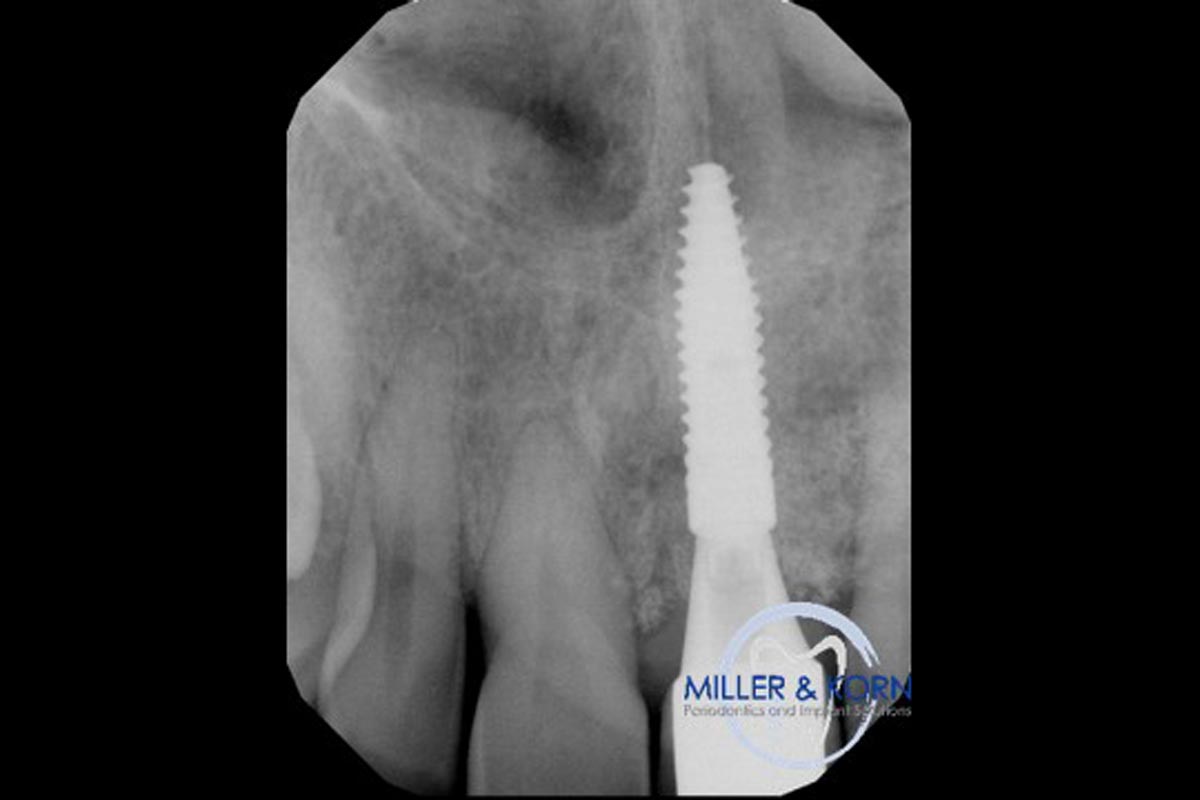

35/39 - Immediate post surgery radiographImmediate implant placement and correction of horizontal and vertical bone loss using an allograft bone ring, cerabone® and Jason® membrane - Drs. Miller and Korn

36/39 - Radiograph 6 months after implantationImmediate implant placement and correction of horizontal and vertical bone loss using an allograft bone ring, cerabone® and Jason® membrane - Drs. Miller and Korn

37/39 - Final radiograph revealing both horizontal and vertical augmentation of the osseous defects (8 months after implantation)Immediate implant placement and correction of horizontal and vertical bone loss using an allograft bone ring, cerabone® and Jason® membrane - Drs. Miller and Korn